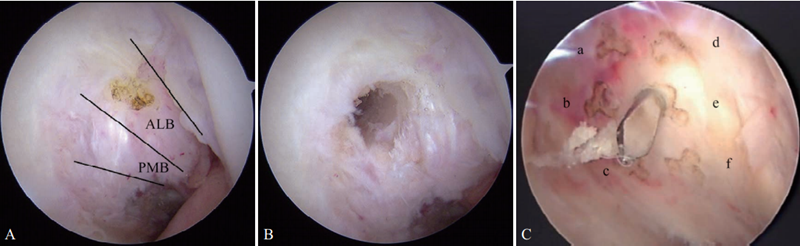

2.制备股骨隧道

从距离髌腱外侧1.5~2.0cm的远前外侧关节镜入路(图2)直视下定位股骨隧道内口。早期文献中PCL股骨选点通常偏前外束止点中心,大约位于股骨髁时钟11点位置(图3 A),距离软骨边缘7~8mm。为了在更偏等长位重建PCL,有研究更倾向于将股骨隧道定位点置于前外束与后内束交界部位,大约位于股骨髁10点30分位置,相当于e点(图3 B、C,图4)。打入定位导针确定位置无误后,制备与移植物同直径隧道。使用界面钉固定移植物时可选择由外向内制备股骨隧道的方法,更利于控制隧道方向和出入口位置。此方法可尽量避免股骨外侧髁软骨损伤,界面螺钉从股骨隧道内口挤入固定移植物。确实需要从内向外制备股骨隧道时(如使用Endobutton需阶梯隧道),采用远前外侧入路比距离髌腱外侧0.5cm的普通外侧入路能使股骨隧道的内口和外侧骨皮质的出口位置更可控(见图2)。

图3 PCL单束重建

A.股骨前外束定位点,远前外侧入路下直视定位,选择前外束(髁间窝11点位置)作为股骨隧道内口定位点;B. 股骨定位点,远前外侧入路下直视定位,选择前外束与后内束交界部位(髁间窝10点30分位置)作为股骨隧道内口定位点;C. 股骨等长定位点,PCL在股骨内侧髁上的止点范围扇形划分为a、 b、 c、 d、 e、 f 6个点,其中e点(髁间窝10点30分位置)与PCL胫骨止点之间最接近等长

图4 PCL单束重建股骨等长定位点示意图(A、B)和测试(C)

[资料来源:KOSUKE O, et al. Measurements of length and tension patterns duringreconstruction of the posterior cruciate ligament. Am J Sports Med, 1992, 20(3):351-355.]